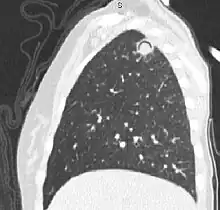

| The arrows denote an ill-defined nodular opacity in medial aspect of right upper lobe with ill-defined rim of lucency surrounding it | |

Sagittal reformat from a CT scan of the chest showing air crescent sign in a patient with invasive fungal infection. There is a rounded cavity in the apical right upper lobe, with a non-dependant soft-tissue nodule within it. Also there is some subtle ground-glass opacity surrounding the lesion.